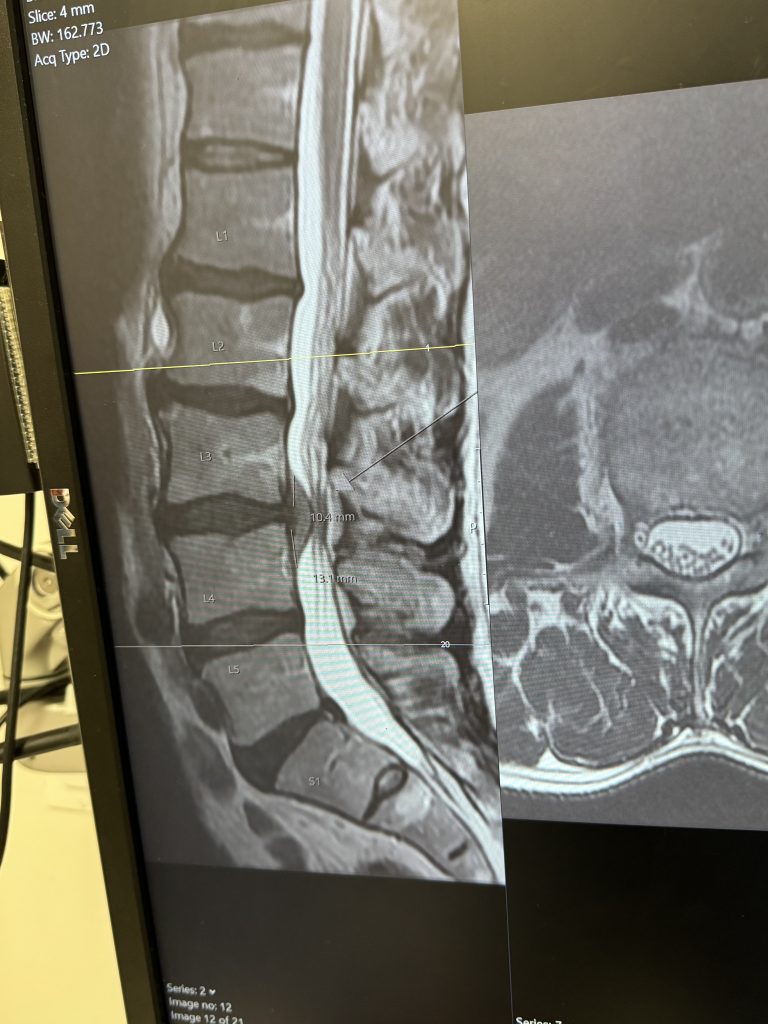

In 2024, I experienced a series of serious injuries. In March, I fractured my pelvis (fortunately, no surgery was required). Then, in August, I suffered a severe herniation of my L3–L4 disc. From that point on, the pain was relentless—shooting from my lower back down my leg - and was excruciating 24/7 from August until my surgery in November 2024.

During that waiting period, I tried physical therapy, massage, chiropractic care, and acupuncture. None provided even the slightest relief. I personally suggested trying an epidural injection—something that was not initially recommended. During the procedure, the space was so tight that they could not administer even half the medication and had to stop due to extreme pain. The clinician at the hospital reviewed my MRI and described the disc as looking like someone had “stepped on a jelly donut,” telling me there was no chance it would resolve on its own - even in six months.

That was when I knew I needed another opinion. A friend’s brother, who is a spine surgeon in Connecticut, reviewed my MRI and confirmed that I would likely need a microdiscectomy. While Connecticut wasn’t feasible for me logistically, I knew exactly where to turn. I had previously had an outstanding experience at HSS with Dr. Riley Williams for knee surgery, and I trusted HSS completely.